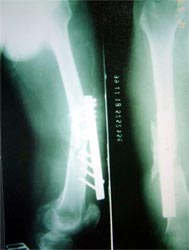

病例一、患者22岁,股骨中下1/3骨折骨不连2年,明显畸形。

X线片显示钢板螺钉已经松脱,固定失败,断端骨折端硬化

我们用髓内钉内固定后保证早期稳定性,植骨补充成骨所需基质,骨生长因子和骨髓细胞的植入,可分化成为骨痂组织,有效促进了骨不连的愈合